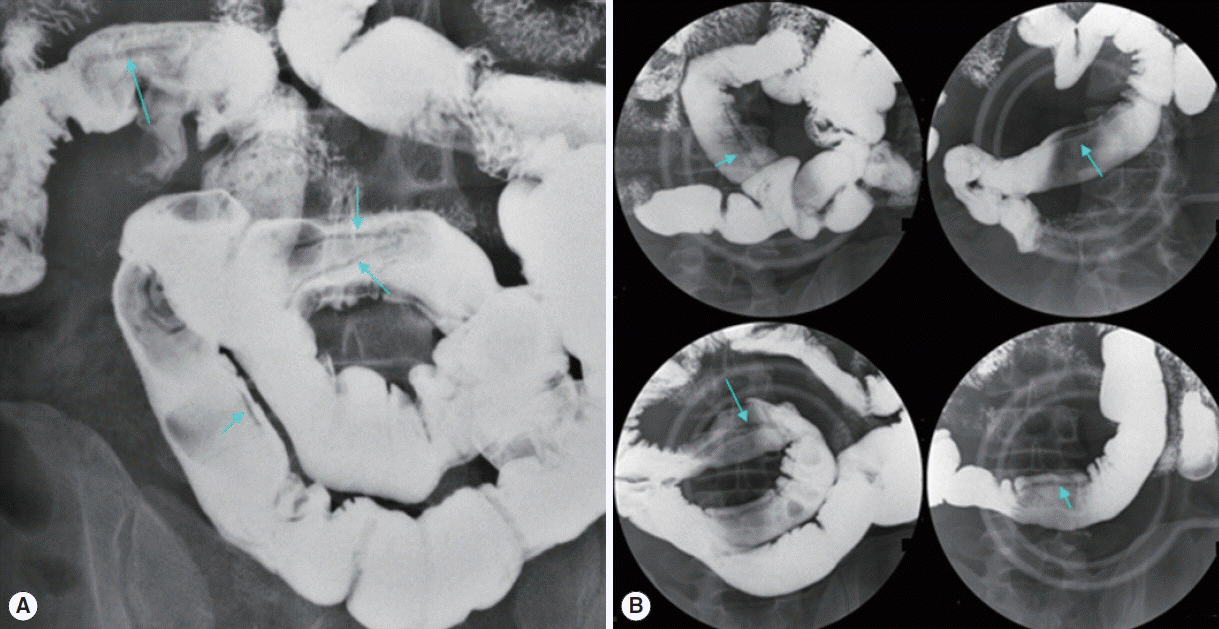

To detect the tapeworm, a small bowel series study was performed. The scolex of the tapeworm could not be identified. However, several flat linear tape-like filling defects were seen from the proximal ileum (Fig. 1). Two more linear filling defects were observed in some regions; some were slender and others were thick. It was unknown whether they were overlappings of a single worm or more than 2 worms. To find out proglottids, the whole defecated stool materials were collected in the large film pouch. However, only 3 pieces of proglottids were collected.